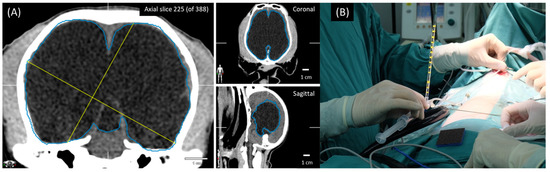

2.1. Treatment

2.2. Follow-Up